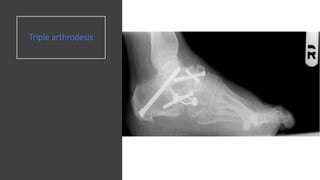

Triple Arthrodesis

Joints fused are:

• Subtalar joint

• Calcaneo cuboid

joint

• Talo navicular joint